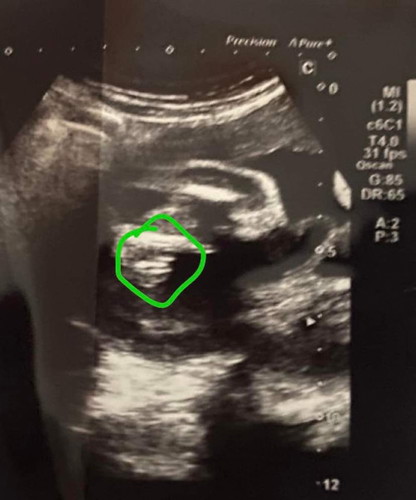

แม่ๆดูออกไหมคะว่าเพศอะไร🙏🤣❤️

น่าจะผู้หญิงนะคะ เป็นสามกีบคาดว่าน่าจะได้ผุ้หญิงค่ะ ของเราผู้ชายจะเป็นแท่งยาวๆ😁